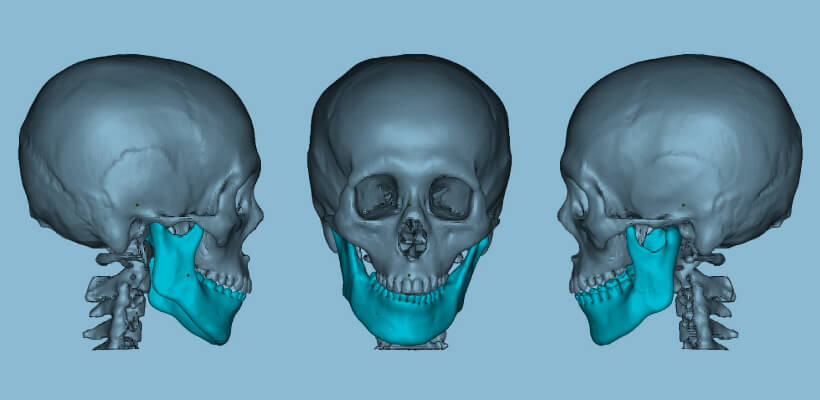

Preoperative simulation

Skull

A full-scale model of the skull can be created from CT data.